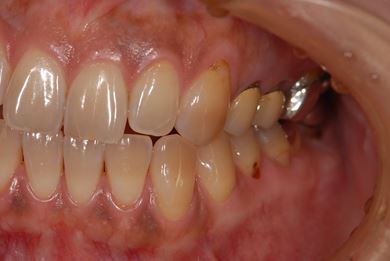

治療後

• 治療後